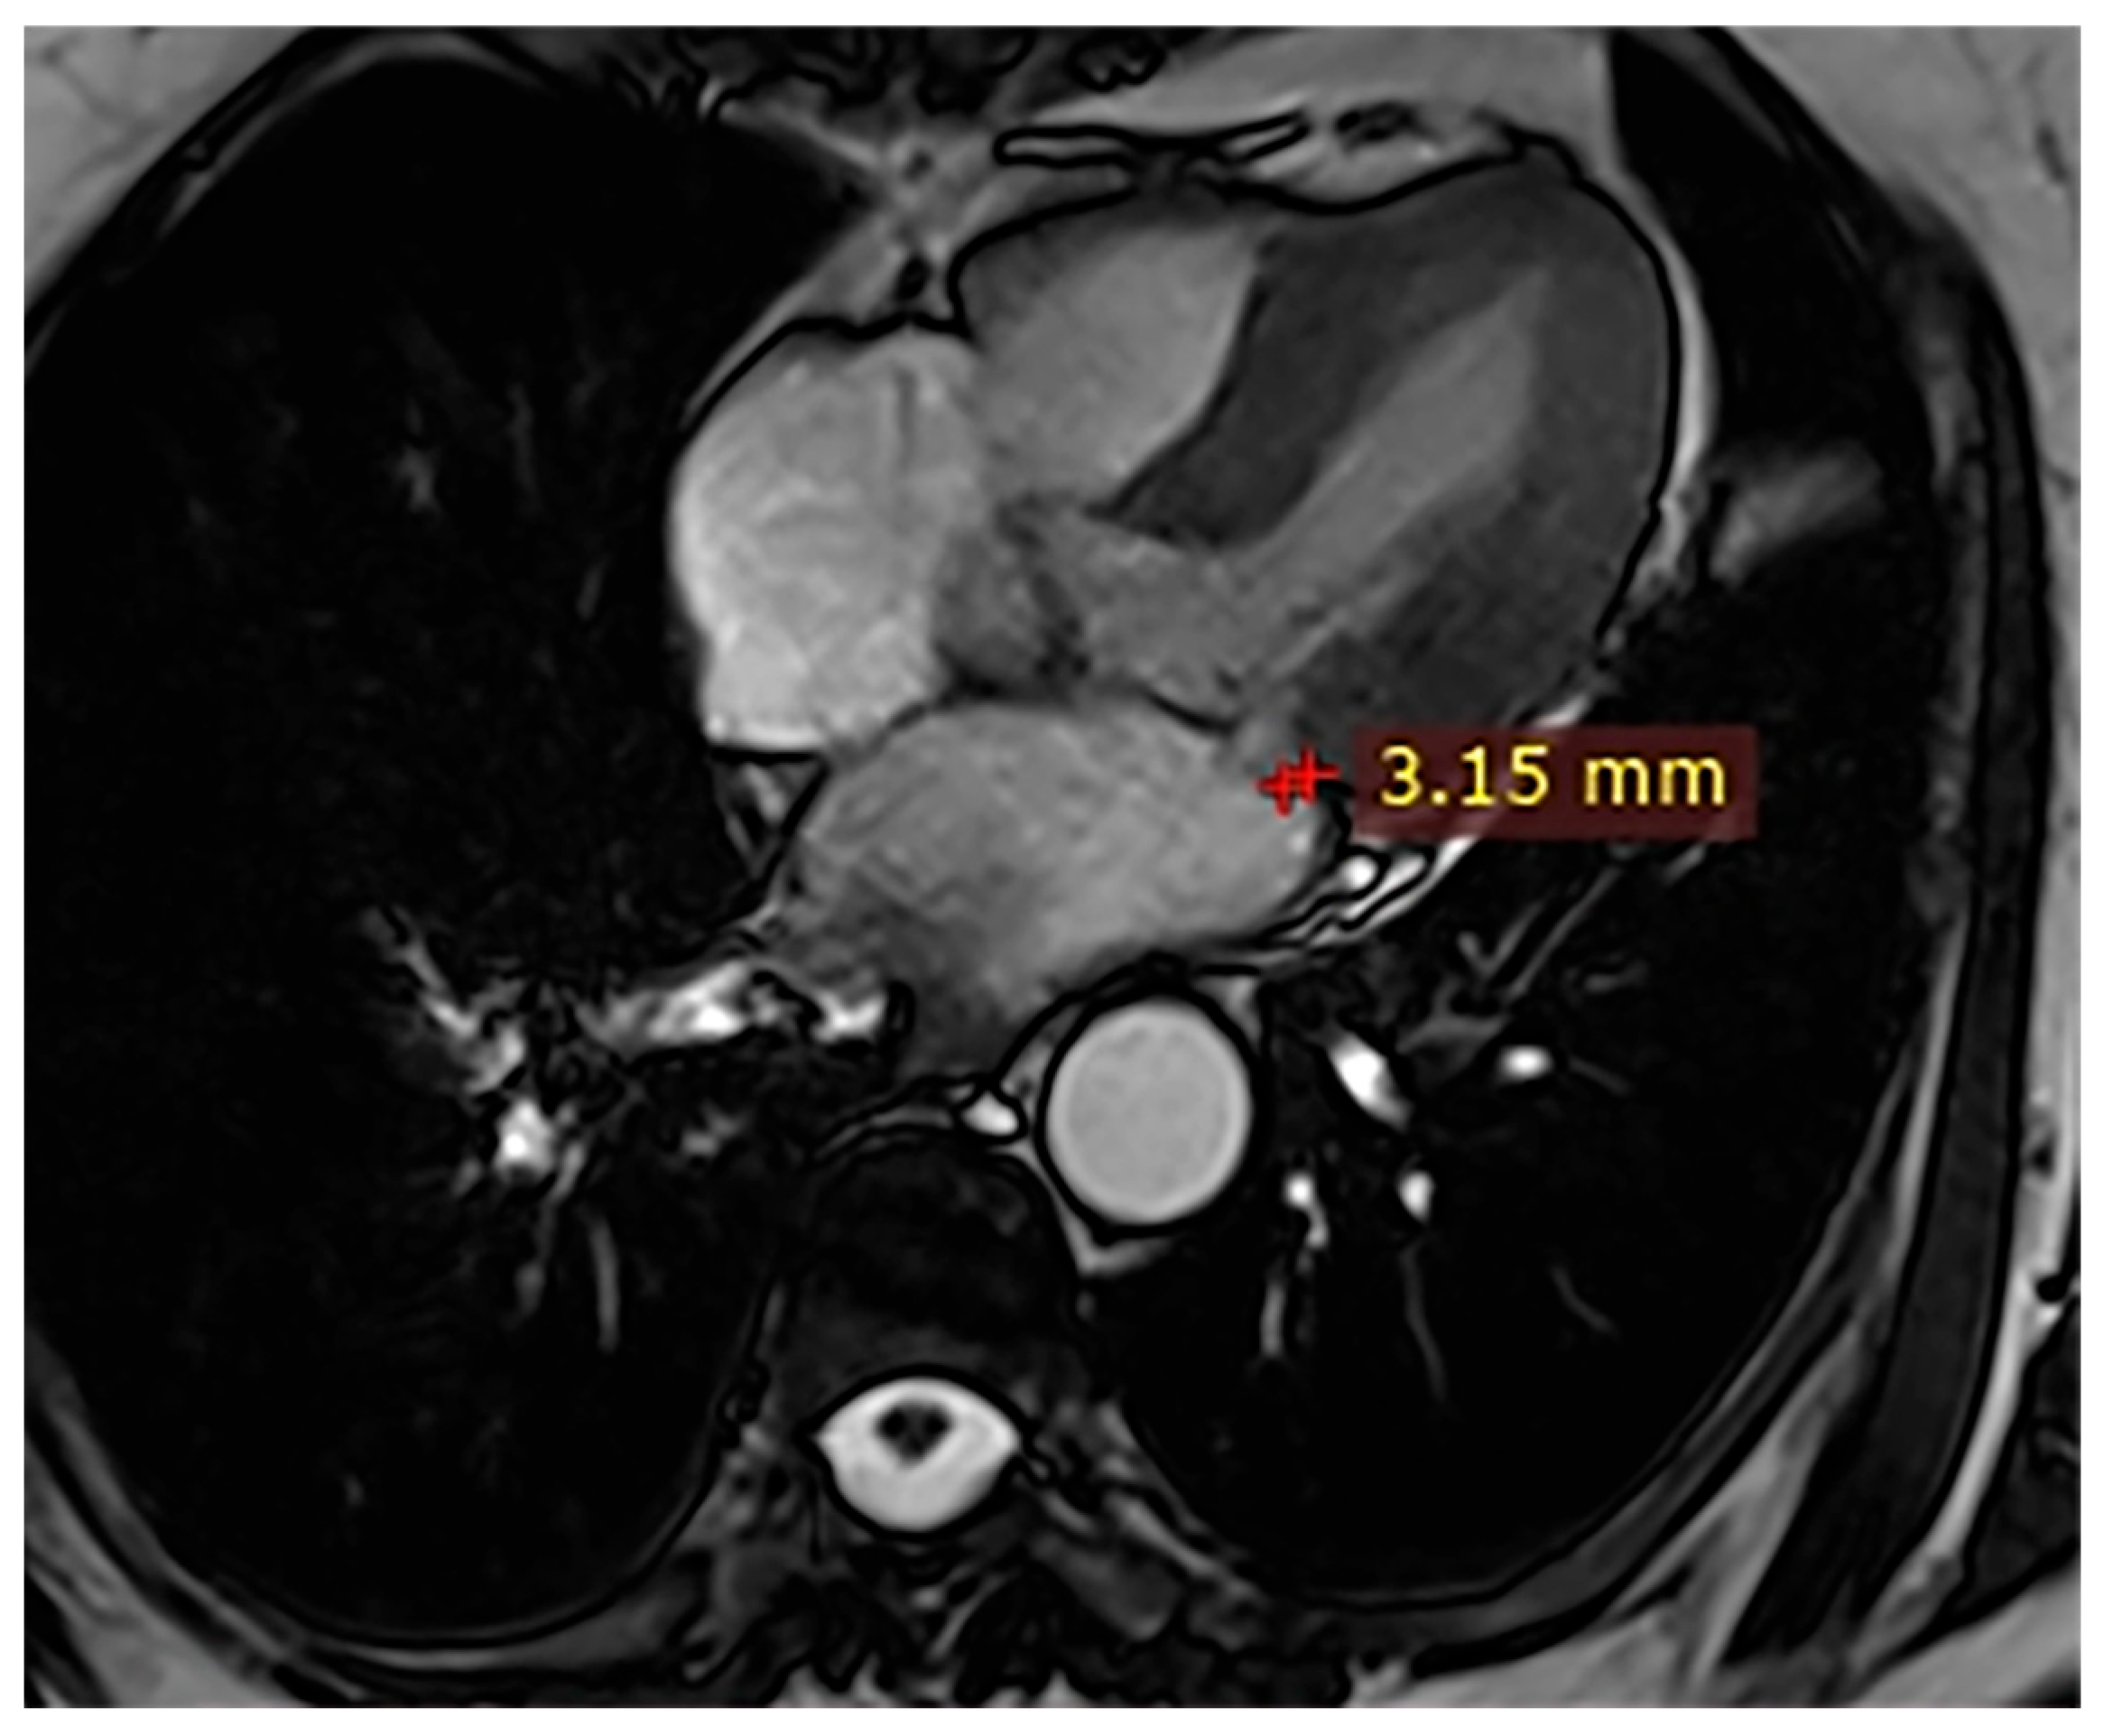

| Case | Patient (Sex, Age) | Symptoms | MAD (mm) | Valvular Issues | LGE | Other Details |

|---|---|---|---|---|---|---|

| 1 | Female, 61 years old | Syncope | 11 | MVP, mitral regurgitation | Lateral | Holter: atrial tachycardia and ventricular ectopy; cardiology follow-up planned for possible mitral valve repair |

| 2 | Male, 52 years old | Syncope and atypical chest pain | 10 | - | Lateral | History of ventricular arrhythmias; cardiology follow-up and Holter monitoring recommended |

| 3 | Female, 74 years old | Extrasystole | 3 | - | No LGE | No LGE; patient reassured and scheduled for periodic clinical follow-up |

| 4 | Male, 34 years old | Extrasystole in Marfan syndrome | 15 | MVP, valvular regurgitation | No LGE | Marfan syndrome; MVP with regurgitation; regular cardiology follow-up advised. |

| 5 | Male, 63 years old | Heart failure | 2,5 | MVP, valvular regurgitation | No LGE | Reduced LVEF (47%) with left atrial dilatation; heart failure therapy optimized; follow-up planned. |

| 6 | Male, 68 years old | Palpitations | 5 | - | Lateral | LGE in basal lateral wall; electrophysiological evaluation and ECG monitoring recommended. |

| 7 | Female, 53 years old | Extrasystole and syncope | 15 | MVP, valvular regurgitation | Basal-lateral | Extensive MAD with MVP and LGE; increased arrhythmic risk; antiarrhythmic therapy considered. |

| 8 | Female, 63 years old | Aortic and mitral regurgitation | 11 | Aortic and mitral regurgitation | Lateral | Aorto-mitral regurgitation with septal hypokinesia; mitral valve repair performed; heart failure therapy started. |

| 9 | Male, 45 years old | Palpitations and vertigo | 10 | - | Lateral | Basal lateral LGE; regular clinical and ECG follow-up recommended |